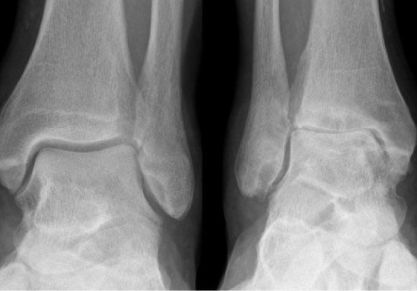

Артроз голеностопного сустава (голеностопа): симптомы и лечение, причины, описание болезни

Что такое артроз голеностопного сустава: симптомы и лечение, причины развития болезни. Диагностические мероприятия, профилактика крузартроза голеностопа.